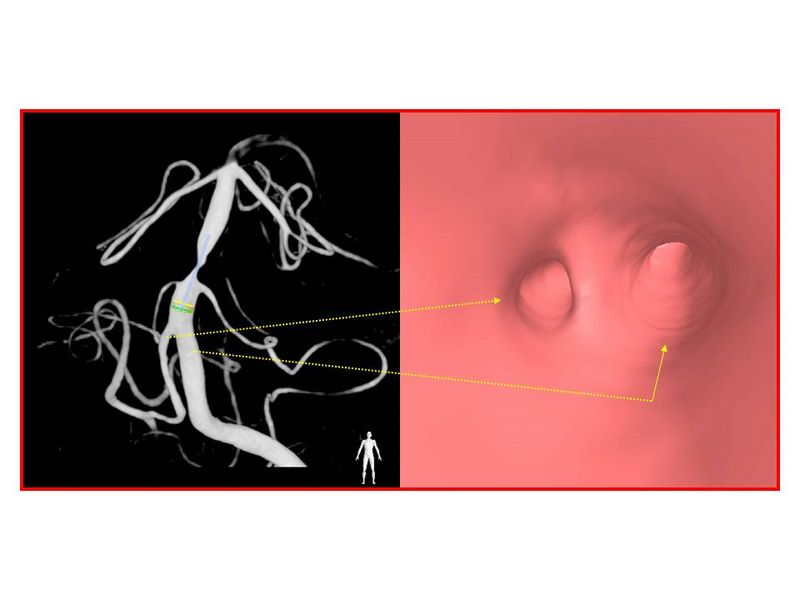

Estenosis Basilar